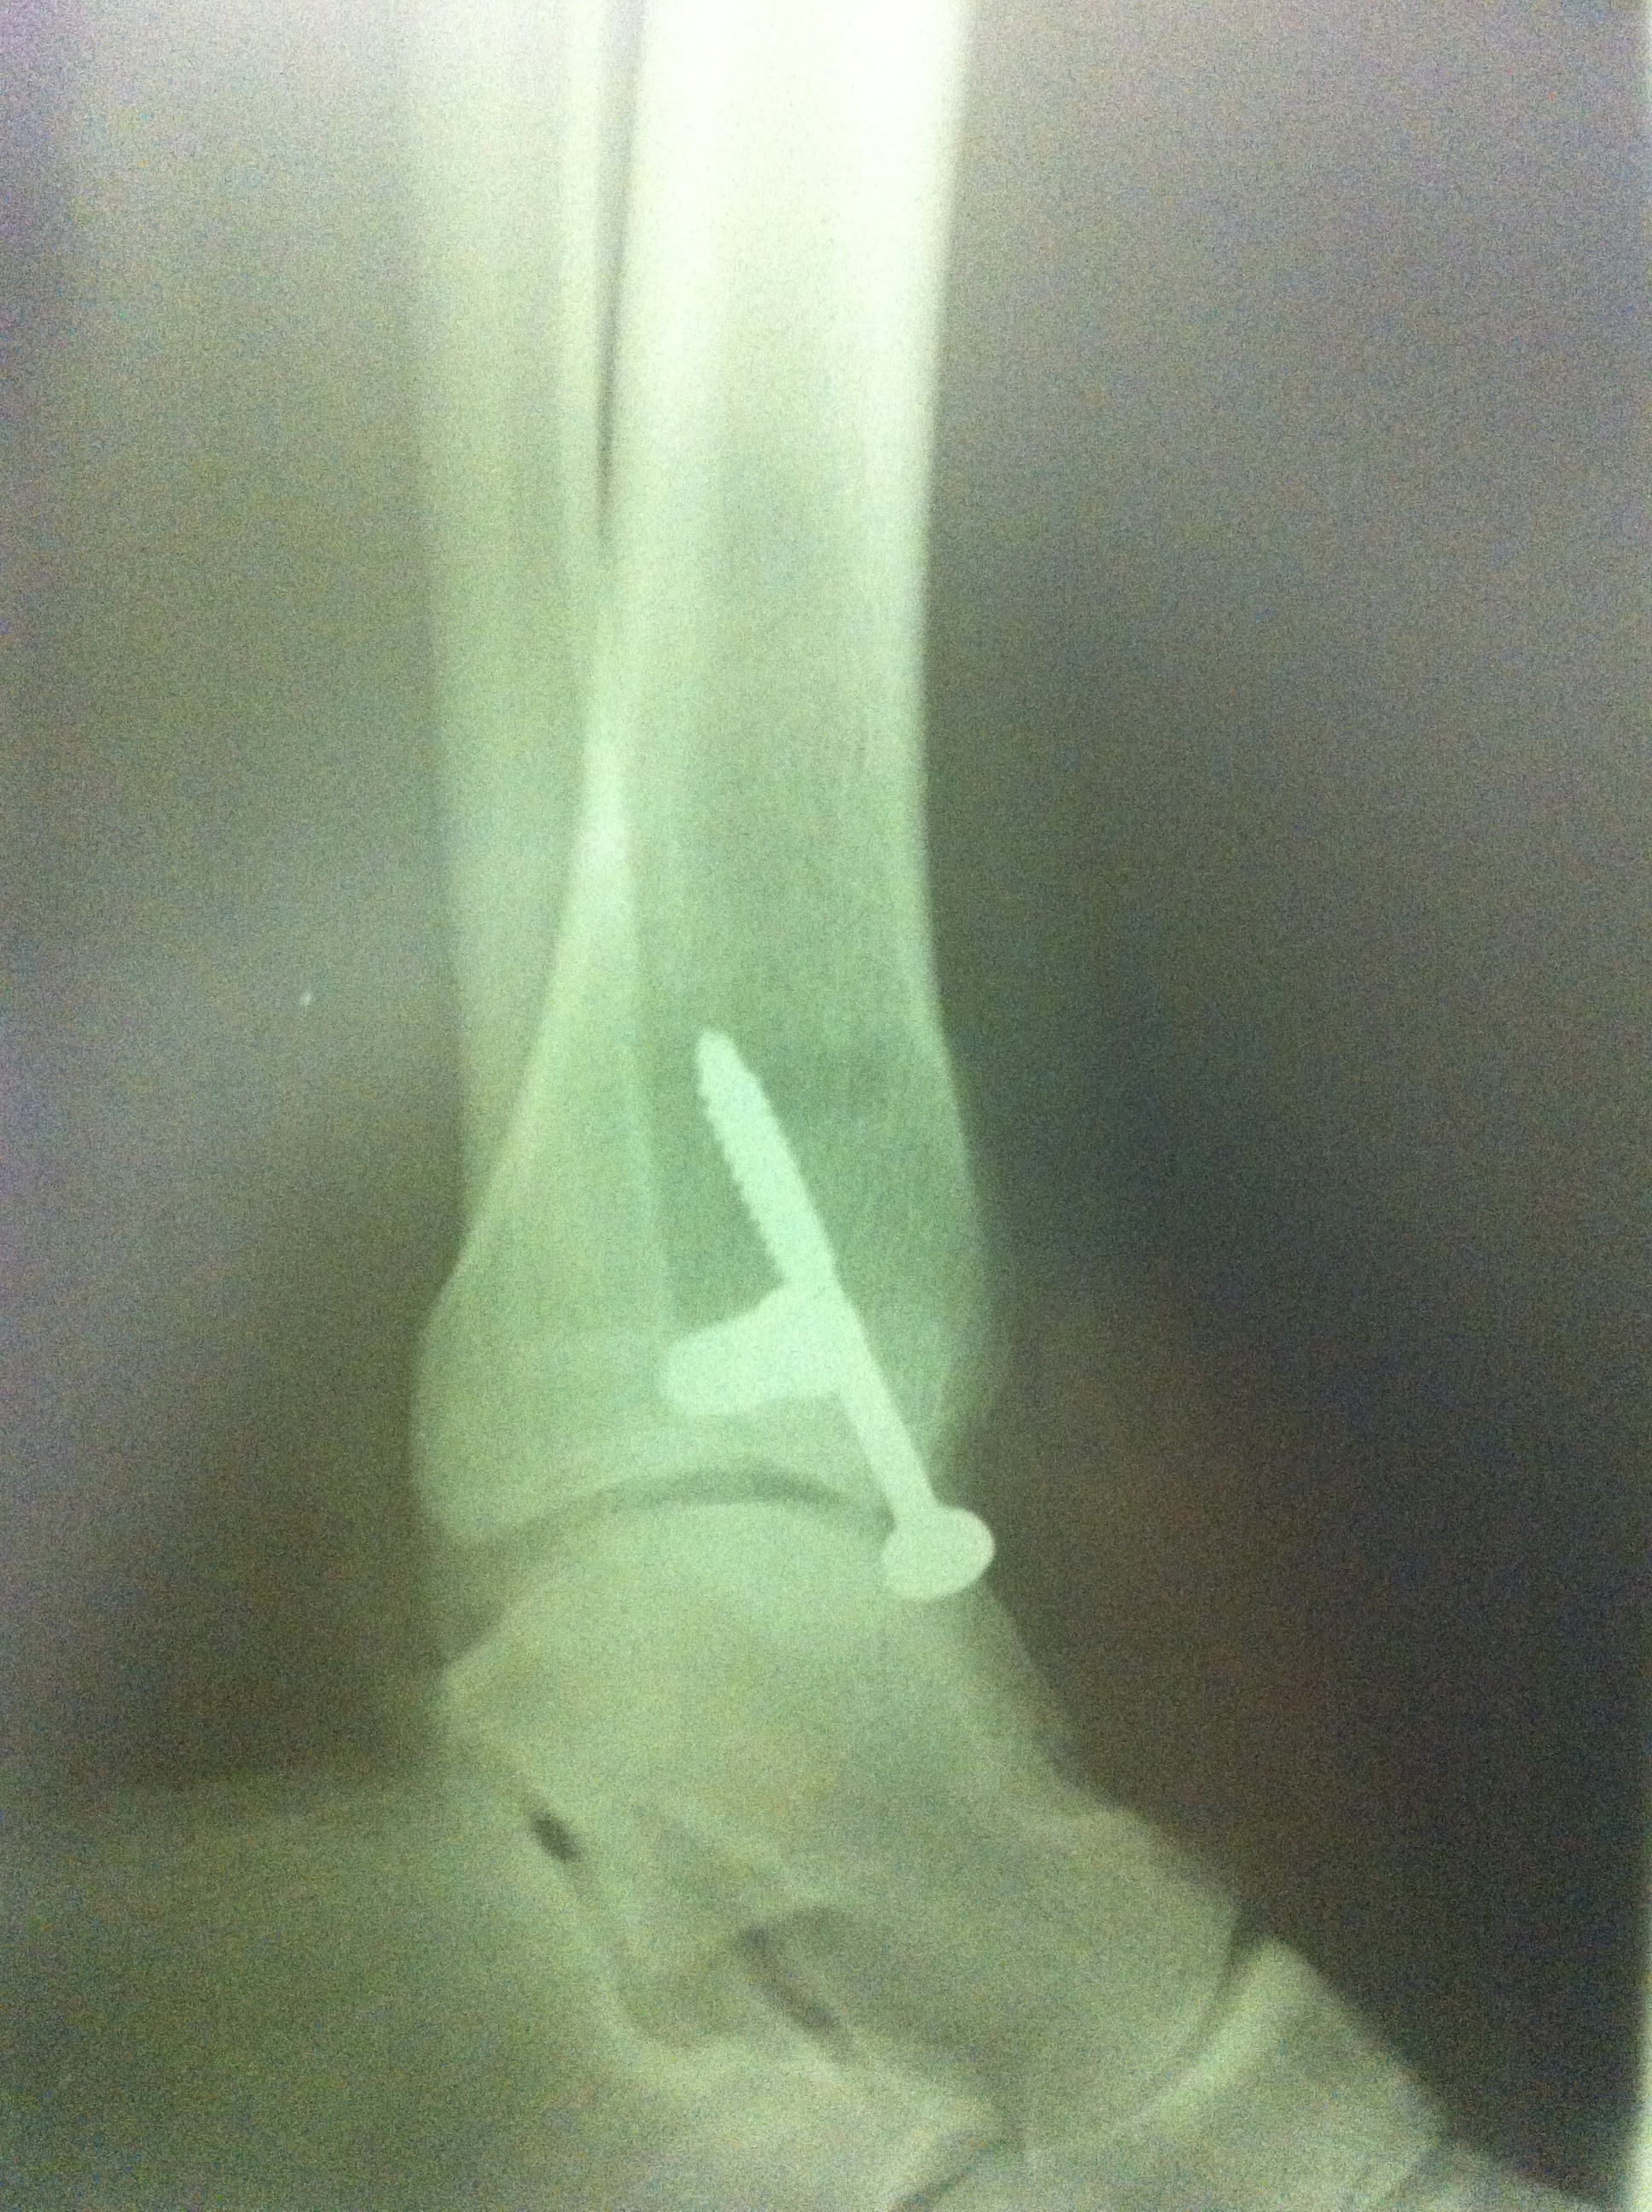

From September to the end of October, I made great progress. My muscles started remembering their previous size and began to grow again. I was on my way to wonderful results, sooner than expected, until an unexpected injury sidelined me, right at the start of November. This was completely unrelated to bodybuilding. We were doing renovations at home, and the workmen had dug a trench in the garden to lay some new pipes. They forgot to tell me. We came back home at night from an out-of-town trip, I took a walk through the garden in pitch black darkness and fell right in. It was a strange feeling, stepping into a void… When my foot hit bottom, I heard a terrible crunch and then the excruciating pain began… The force of the impact pulled on my ankle ligaments so much that it fractured both the tibula and the fibula at their ends. (The medical term is bimalleolar fracture.) It snapped one of them clean off and the other managed to hang on.  Let’s just say I have a nice zipper-shaped scar on my ankle and a couple of extra titanium screws in there. I’m thankful that the ligaments didn’t tear, because the recovery would have been more painful and would have lasted longer. Here’s the x-ray after surgery.